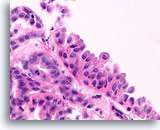

Papilloom, Borst FNA, Celblok.

Met een sterkere vergroting kan een gemengde celpopulatie gezien worden die het oppervlak en de onderliggende melkgangen bekleden. Een rij myoepitheliale cellen is zichtbaar tussen de ductale cellen en het onderliggende stroma (pijl). Let op de spleetachtige ruimte die kenmerkend is voor typische hyperplasie (open pijl).

Papilloom, Borst FNA, Celblok.

Met een sterkere vergroting kan een gemengde celpopulatie gezien worden die het oppervlak en de onderliggende melkgangen bekleden. Een rij myoepitheliale cellen is zichtbaar tussen de ductale cellen en het onderliggende stroma (pijl). Let op de spleetachtige ruimte die kenmerkend is voor typische hyperplasie (open pijl).